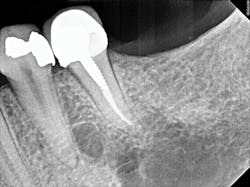

Figure 3: A periapical radiograph showing tooth No. 22 with a radiolucency near the apex, which looked small relative to the areas on Nos. 20 and 21. There is also distortion of the appearance of the mental foramen in the area.